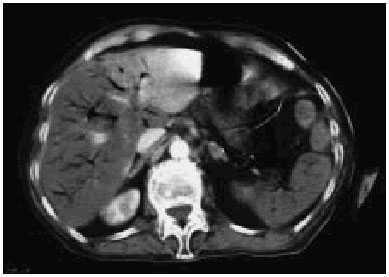

La tomografía axial computarizada (TAC) abdominal puso de manifiesto imágenes de neumatosis intestinal, distensión abdominal, abundante gas en la vena mesentérica y sistema portal (vena porta y esplénica), compatible con isquemia mesentérica grave (figs. 1 y 2).

Fig. 1.